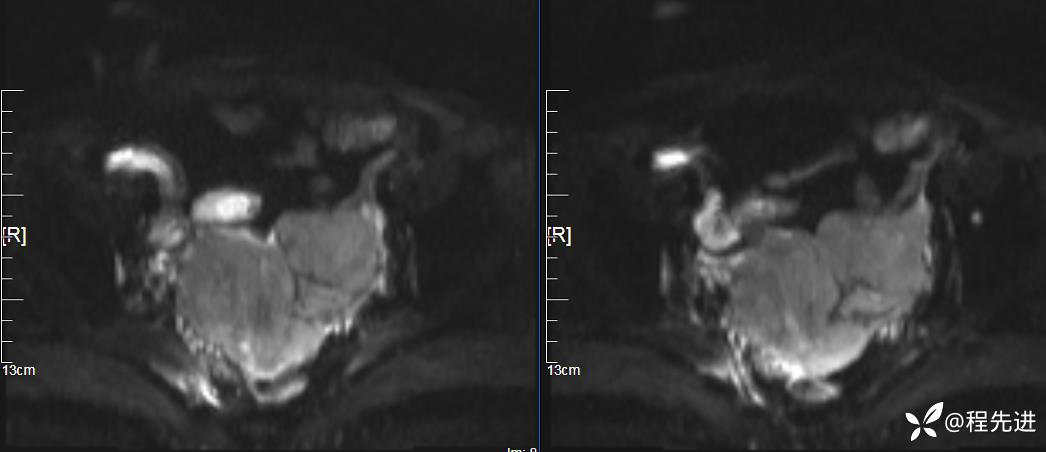

DWI、ADC: